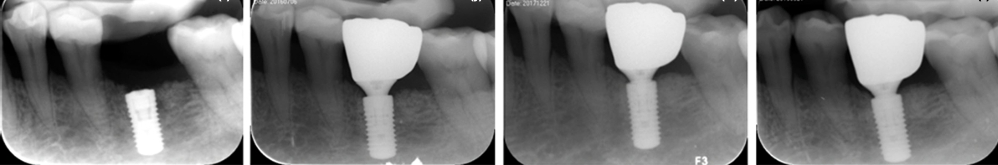

接受拔牙同期牙槽嵴保存术的患者种植手术后即刻、种植修复后1年、2年、3年随访X线片,种植体边缘骨水平稳定,证实牙槽嵴保存术后种植修复体可维持长期健康